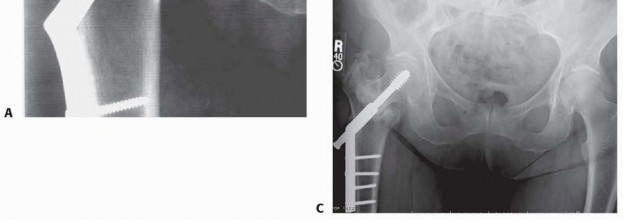

POSTOPERATIVE CARE 413 AP and lateral radiographs of the operative hip should be obtained immediately postoperatively in the recovery room to assess implant position and fracture reduction and to ensure that no iatrogenic femur fracture was produced intraoperatively. The entire device should be included in the radiograph ( FIG 6). Patients are mobilized as soon as their cardiopulmonary and mental status will safely allow, usually by postoperative day 1. Unrestricted immediate postoperative weight bearing is easiest for the patient to comply with, and multiple investigations have shown no increase in fixation failure as a result of this postoperative rehabilitation protocol. 8 Koval et al 7 used gait analysis to show how patients effectively autoregulate their weight bearing postoperatively, with the patients who had the least stable fracture patterns preoperatively putting the least amount of weight on their legs immediately postoperatively. Patients should be seen 2 weeks postoperatively to check for uneventful wound healing. Follow-up radiographs should be obtained at 2, 6, and 12 weeks to check for controlled fracture impaction, exclude any fixation device complications, and assess fracture healing. ## OUTCOMES With proper fracture reduction, implant selection, and fixation device positioning, peritrochanteric hip fractures heal in up to 98% of cases. One-year mortality rates after fixation of peritrochanteric hip fractures range from 7% to 27%, with most studies finding a rate of 15% to 20%. 11 According to Medicare data, 30-day and 180-day mortality rates continue to improve. Mortality rates depend on both preoperative and postoperative medical complications and condition as well as preoperative functional status. Postoperative functional status also depends on numerous variables: Socioenvironmental functional status has been shown to be of great importance in determining the postoperative function status of a patient. 11 ### FIG 6 • Postoperative AP (A) and lateral (B) radiographs showing correct implant positioning and no intraoperative complications. Longitudinal studies comparing the functional status of patients before and after hip fracture fixation have documented that roughly 40% of patients maintain their preoperative level of ambulation postoperatively. Another 40% of patients have increased dependency on ambulation devices but remain ambulatory. Twelve percent of patients become household-only ambulators, and 8% of patients become nonambulators postoperatively. 6

COMPLICATIONS Loss of proximal fixation is defined as varus collapse of the proximal fracture fragment with cutout of the lag screw from the femoral head ( FIG 7A). This complication is seen in 4% to 20% of fractures, usually within 4 months of surgery. Although certain fracture patterns have been shown to have a higher rate of proximal fixation loss, the fracture pattern cannot be controlled by the physician. The placement of the lag screw, on the other hand, can be controlled by the physician. A central and deep position with a tip-apex distance of less than 25 mm has been shown to significantly reduce the incidence of proximal fixation loss. 2 Nonunion occurs in 1% to 2% of fractures. The low incidence is likely due to the well-vascularized nature of the cancellous peritrochanteric region of the hip through which these fractures develo Secondary fracture displacement Despite adequate fracture reduction and implant positioning, fractures may progress to excessive impaction, with resultant limb shortening and abductor weakening ( FIG 7B,C). This can lead to suboptimal patient functional results. This is often seen in cases of unrecognized lateral wall fractures (either iatrogenically induced by implant placement or unrecognized from the original trauma). Use of intramedullary fixation devices and vigilant followup may help avoid this complication. Infection Wound dehiscence 414 ### FIG 7 • A. Varus collapse. B. AO/OTA type 31-A1 peritrochanteric hip fracture fixed with a sliding hip screw. C. Followup radiograph 6 months postoperatively showing secondary fracture displacement.